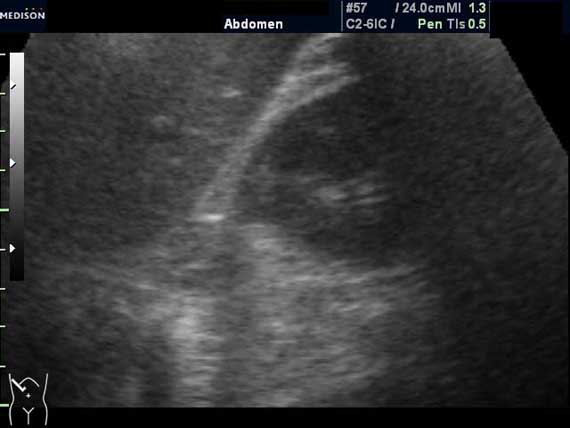

Женщина 50 лет. Жалоб нет. Обследование перед поездкой в санаторий по поводу дисфункции гепатобилиарной системы.

Случайная находка в нижней трети левой почки (не в полюсе, а по задне-медиальной поверхности).

ПО УЗ-семиотике образование соответствует ангиомиолипоме (AML). По правилам в таких случаях необходимо выполнить КТ, доказать преимущественно жировой состав опухоли, затем проводить УЗ-наблюдение.

Согласен. Именно с таким диагнозом (ангиомиолипома) отправил на КТ. Особенностью случая ИМХО является заметный "выход" образования за контур почки (на 2/3 объема).

При ультрасонографии ангиомиолипома выглядит как округлое образование без капсулы с однородной внутренней эхоструктурой и четкими контурами; эхогенность ее чаще всего равна или чуть выше эхогенности перинефральной клетчатки [7]. Значительно реже эхогенность ангиомиолипом может быть равна эхогенности почечной паренхимы; такие опухоли состоят почти полностью из гладкомышечной ткани [8]. Иногда позади ангиомиолипомы может определяться слабая акустическая тень.

Выполнена КТ. Заключение: липома.